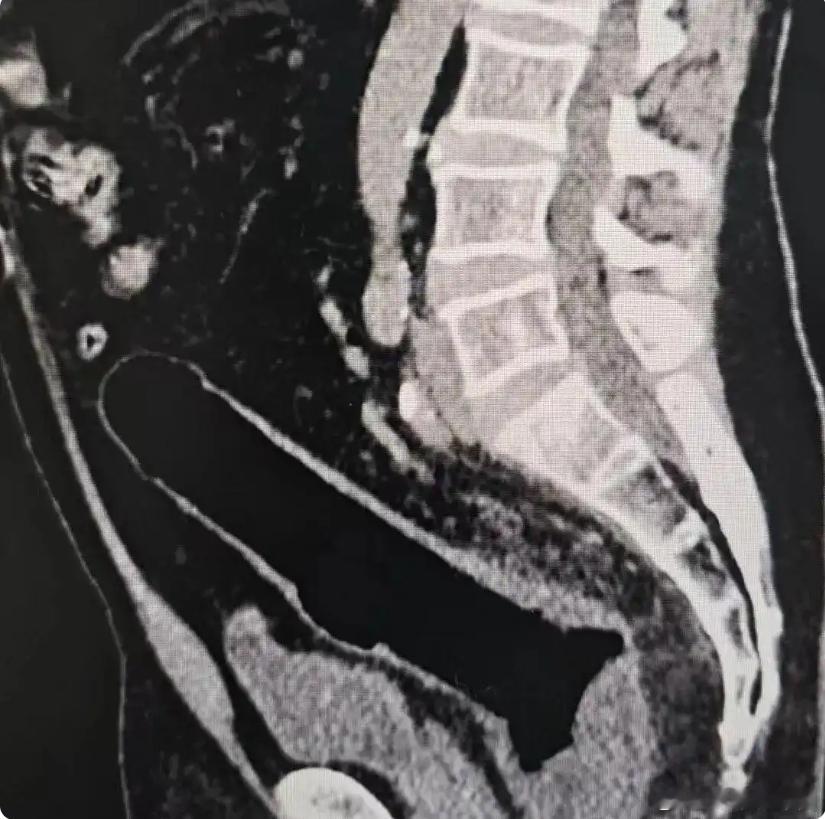

深圳一位中年男子到医院说自己“不小心把玩具坐了进去”事情导致他肠道穿孔,医生只能为其手术,把异物成功取出但男子还是得接受肠道造口手术,等3个月到半年再做手术才能恢复又是一个阴阳人烂屁股